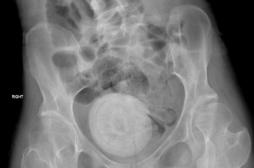

LES MALADIES

J'AI MAL

SYMPTÔMES